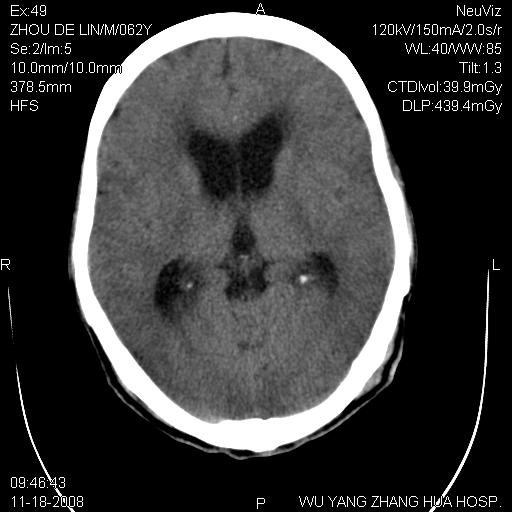

患者近段时间偶有头晕,无其他不适。既往有糖尿病病史。

小脑中线区见一类圆形混杂密度影,四脑室受压变形,其后方见一边界清楚的囊性低密度影,幕上脑室扩张。小脑中线区肿瘤,儿童多见于髓母细胞瘤,成人多见于胶质瘤。

诊断:小脑胶质瘤可能性大。建议增强扫描

支持,病灶似位于四脑室内,不除外四脑室室管膜瘤,发生几率也较高

小脑囊实性占位病变、脑室系统积水扩张、脑肿胀。

小脑囊实性占位病变、脑室系统积水扩张,建议增强

诊断:小脑胶质瘤可能性大。建议增强扫描。支持!

1)小脑蚓部(偏左侧)占位性病变;不排除转移瘤可能。建议行进一步检查。2)脑积水。